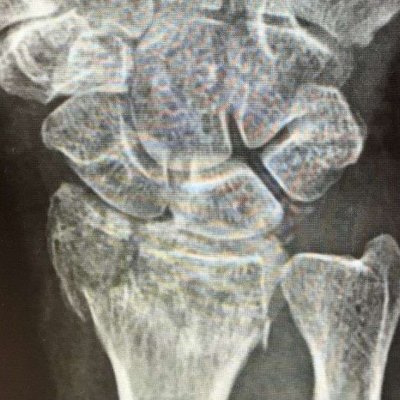

Distal-radius-fractures

A recent study reported that distal radius fractures represent 16.4% of all broken bones making it one of the most common fractures. Thankfully, many patients respond well to immobilization –  using either a cast or splint depending on the severity of the injury.

Currently there is moderate evidence supporting surgery as a way to improve outcomes in patients younger than 65 with appropriate radiographic criteria, including radial height loss, dorsal displacement, and intra-articular displacement. For these candidates, a surgeon can utilize many different surgical options to return the bone to its original anatomic position.